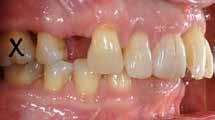

Der planlægges alignerbehandling af begge kæber med intrusion af 1+1 og 2,1-1,2, nivellering af trangstilling UK med interproksimal reduktion (IPR) (Fig. 2 A, B) og senere IPR OK for reduktion af dark triangles mellem incisiverne efter nivellering. Patienten instrueres i at benytte alignere 20-22 timer/ dag med alignerskift hver 7. dag, og patienten ses hver 3.-8. uge under forløbet. Den første alignerserie består af 16 alignere for nivellering OK/UK og IPR i UK (Fig. 2). Efter denne serie planlægges IPR mellem incisiverne i OK for reduktion af dark triangles (Fig. 3) samt yderligere intrusion af OK og UK-fronten i 12 refinement-alignere. Patienten udviser god kooperation og er meget tilfreds med alignerapparaturet, som er mindre synligt end det faste apparatur (Fig. 4).

Behandlingen afsluttes med yderligere refinement-alignere for finindstilling af okklusionen, og efter 11 måneders ortodontisk behandling er der opnået normale relationer i alle tre